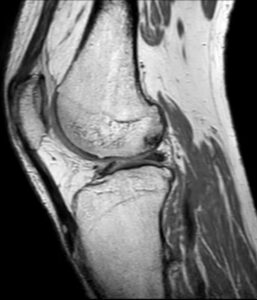

A ressonância magnética (RM) ao joelho é um exame que utiliza campos magnéticos e ondas de radiofrequência para gerar imagens de elevada resolução das estruturas internas da articulação, incluindo ossos, cartilagens, meniscos, ligamentos e tendões. É especialmente útil na deteção de lesões que não são visíveis em exames como radiografias ou tomografias computorizadas (TACs).

A ressonância magnética ao joelho permite identificar com grande precisão:

- Roturas dos ligamentos cruzados (anterior e posterior) e colaterais;

- Lesões dos meniscos medial e lateral;

- Condropatias e desgaste da cartilagem articular;

- Tendinites e roturas dos tendões rotuliano e quadricipital;

- Bursites e derrames articulares;

- Quisto de Baker;

- Fraturas ocultas e alterações do osso subcondral;

- Tumores ou massas intra-articulares;